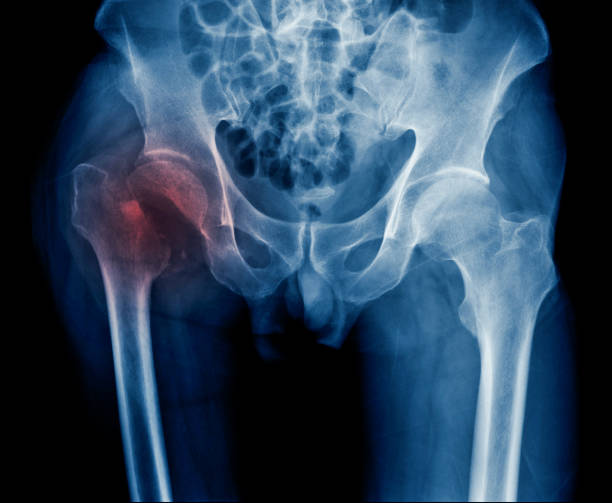

고관절 수술후 회복기간- 수술 후 2주~6주: 물리치료 및 근력 강화

2주~6주 동안은 물리치료와 근력 강화에 집중해야 합니다. 수술로 약화된 근육을 다시 강화하고, 동작 범위와 적응력을 향상시키기 위한 운동을 실시해야 합니다. 이때 꼭 전문가의 도움을 받아야 하며, 개인 차원에 맞는 프로그램을 진행해야 합니다. 무리한 운동을 하지 않도록 조심해야 합니다.